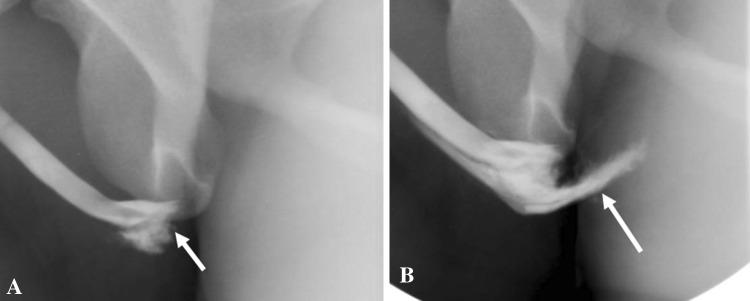

To discuss the imaging appearances of various pathologies affecting adult male urethra and to review the role of imaging in the assessment of artificial urinary sphincters and penile prostheses. Diagnosis of common male urethral diseases heavily depends on two conventional fluoroscopic techniques namely retrograde urethrography and voiding cystourethrography. These are useful in evaluating common urethral diseases like traumatic injury, infections, and strictures. Cross-sectional imaging can be useful in evaluating periurethral pathologies. Artificial urinary sphincters, slings, and periurethral bulking agents are used in the management of urinary incontinence and imaging can be utilized to detect complications in these devices. Cross-sectional imaging especially MRI plays a significant role in evaluating the different types of penile prostheses and their malfunctioning.

讨论影响成人男性尿道的各种病变的影像学表现,并回顾影像学在评估人工尿道括约肌和阴茎假体中的作用。常见男性尿道疾病的诊断主要依赖于两种常规的荧光透视技术,即逆行尿道造影和排尿性膀胱尿道造影。这些技术在评估外伤性损伤、感染和狭窄等常见尿道疾病方面非常有用。横断面成像可用于评估尿道周围病变。人工尿道括约肌、吊带和尿道周围填充剂用于治疗尿失禁,影像学可用于检测这些装置的并发症。横断面成像,特别是 MRI,在评估不同类型的阴茎假体及其故障方面发挥着重要作用。